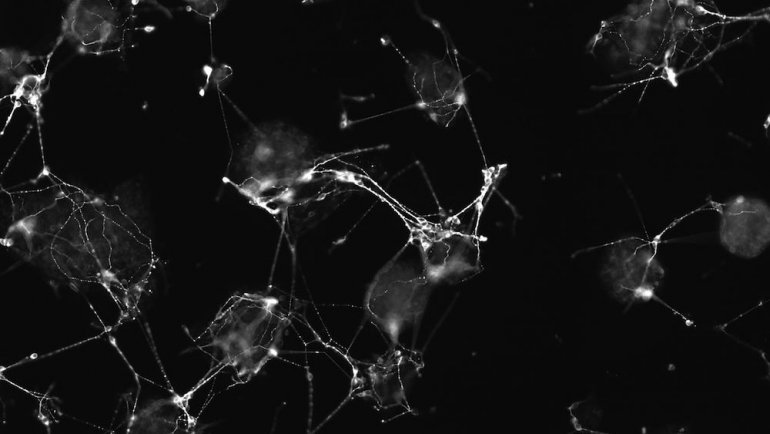

Bu videoda kök hücrelerinden 96 saatte bir beyin oluşuyor. Harikulade.

Son yıllarda kök hücre teknolojisindeki ilerlemeler çığır açıcı nitelikte. Kaliforniya üniversitesi tarafından hazırlanan bu videoda farelerin kök hücreleri ile yapılan bir deney var. Videonun başında göreceğiniz kök hücre kümelerinin her bir tanesinin içerisinde 10 kadar hücre var ayrıca bu hücreler genetik olarak değiştirilip ışığa duyarlı hale getirilmiş. Bu hücreler bir süre sonra ışıkla harekete geçmeye

Ohio Devlet Üniversitesindeki bilim adamları bir tabakta bir insan beynini, cilt hücrelerinden oluşturmayı başardılar. Bu beyin 5 aylık bir fetüsün olgunluğuna sahip.

Bu beyin organımsısı yetişkin insan cilt hücrelerinden dönüştürülmüş ve şu ana kadar oluşturulabilen en tam beyin modeli Ohio Devlet Üniversitesi’nde biyolojik kimya profösörü olan Rene Anand’a göre. Laboratuvarda üretilen beyin bir kalem silgisi büyüklüğünde, ve bebek beyninde bulunan gen ve yapıların yüzde 99’unu içerisinde barındırıyor. Böyle bir sistem hem etik hem de hızlı bir şekilde